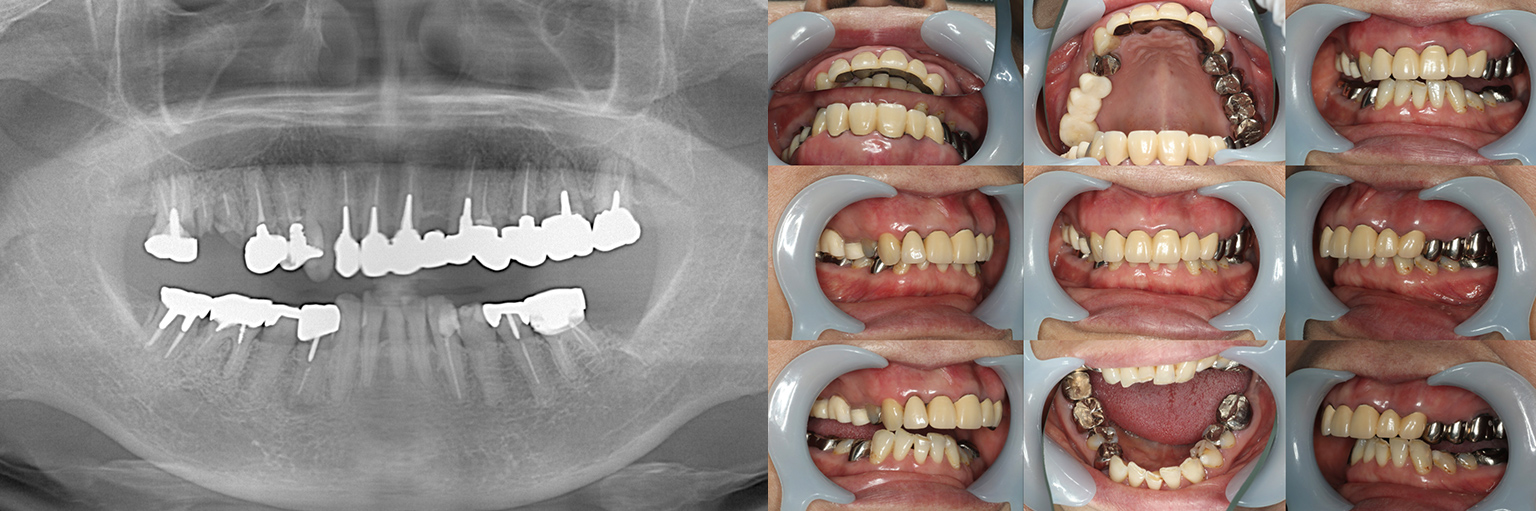

【治療例 1】全体的に見て欲しい 67歳

全体的に診て欲しい、ということで来院されました。歯が痛くなるたびに歯医者には通っていたが、噛み合わせをちゃんと治療したことはないとおっしゃっていました。

上記のように

①しっかりと噛めること

②持続すること

③修理しやすいこと

をポイントに治療計画を相談させていただきました。 - 治療費用・方針

写真の通りに治療を終了いたしました。

上顎は総義歯の形態に、下顎は十分な寿命を持った歯は残して、長期的な保存が難しい歯はインプラント治療を施しました。上顎を総義歯形態にすることにより、何かが起こっても義歯の修理を行えば対応が可能です。即日の修理・完了も難しくないでしょう。

下顎は十分な寿命を持った歯しか残していないので、今後の人生でよっぽどのことがない限りトラブルが起きないと考えます。インプラント治療を施してある部分も、同様にトラブルが起きにくいと考えています。歯周病になった、とか歯が欠けた、というインプラント治療の悪い面が聞こえてくるようになりましたが、噛み合う上の歯を総義歯とすることで、過大な力がかかることなく、トラブルが起きにくい結果を得ることができました。

上顎は総義歯ですが、『今まで食べられなかったものがなんでも噛めるようになった』と、患者さんよりお言葉を頂戴しております。

【治療例 2】金属を白くしたい63歳

右上の奥歯が取れたということで来院されました。

各所の金属は昔に治療されたもので、外してみるとどれも虫歯になっていました。

一つずつ虫歯治療を行い、インプラント治療、矯正治療を並行して行いました。 - 治療費用・方針

各所虫歯に侵食されていましたが、歯を残すことができたのでインプラントの数をおさえることができました。

下の前歯が先天的に1本欠損しており、そのため噛み合わせを構築することが難しいケースでした。矯正治療を併用することで前歯と奥歯をバランスよく噛ませることに成功しました。